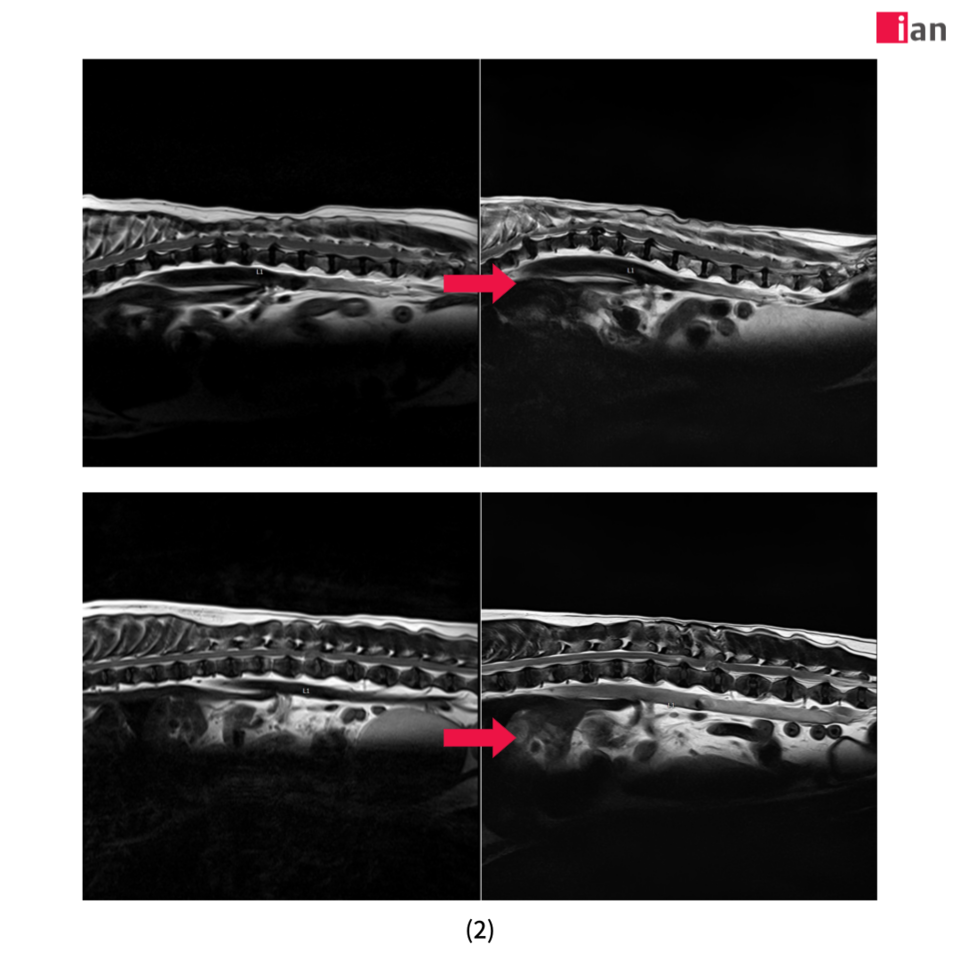

2023년 말 최첨단 AI MRI 소프트웨어를 도입한 이안동물의학센터는 촬영 시간 단축과 영상 품질 극대화라는 두 마리 토끼를 동시에 잡았다. 딥러닝 알고리즘을 통한 이미지 재구성과 노이즈 제거, 선명도 향상은 보다 신속하고 정확한 진단을 가능하게 했으며, 보호자와 반려동물 모두에게 높은 만족도를 제공하고 있다.

특히 AI 소프트웨어 도입 이후 촬영 시간이 기존 대비 최대 절반으로 줄어드는 등 검사 효율성이 크게 향상됐다. 이는 보호자들의 시간적 부담을 덜어줄 뿐 아니라 환자의 마취 시간 단축으로 검사 안전성을 더욱 높이는 효과를 가져왔다.

또한 이미지 퀄리티 향상으로 정밀한 판독이 가능해져 질병의 조기 발견과 정확한 진단을 통한 치료 전략 수립에 커다란 진전을 이뤄냈다. 여기에 이안동물의학센터 전담 마취팀의 철저한 관리까지 더해져 반려동물 검사 전 과정에서 신뢰도 높은 의료 서비스를 제공하고 있다.